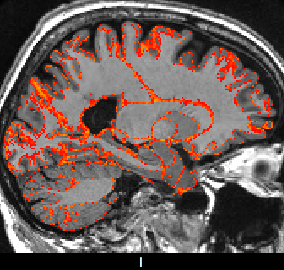

This section investigates the number of Monte Carlo samples and the segmentation performance of the proposed network. Fig. 8(a) suggests that using samples is enough to achieve good segmentation. Further increasing the number of samples has relatively small effects on the DCS. Fig. 8(b) plots the voxel-wise segmentation accuracy computed using only the voxels with an uncertainty less than a threshold. The voxel-wise accuracy is high when the threshold is small. This indicates that the uncertainty estimation reflects the confidence of the network. Fig. 9 shows an uncertainty map generated by the proposed network. The uncertainties near the boundaries of different structures are relatively higher than the other regions.

With this theoretical insight, we are able to estimate the uncertainty of the segmentation map at the voxel level. We extend the segmentation network with a convolutional layer before the last convolutional layer. The extended network is trained with a dropout ratio of 0.5 applied to the newly inserted layer. At test time, we sample the network N times using dropout. The final segmentation is obtained by majority voting. The percentage of samples which disagrees with the voting results is calculated at each voxel as the uncertainty estimates.